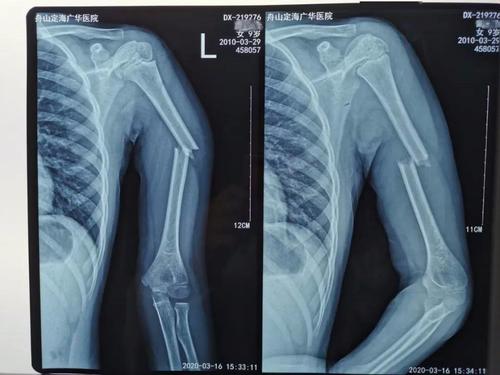

术后c型臂x光透视,骨折对位对线良好,桡腕关节面复位光滑,达解剖复位.

术精岐黄|11岁女孩手臂卷入洗衣机致骨折 医生微创手术巧复位_手机

石家庄市三院成功治疗高龄老年肱骨近端粉碎骨折